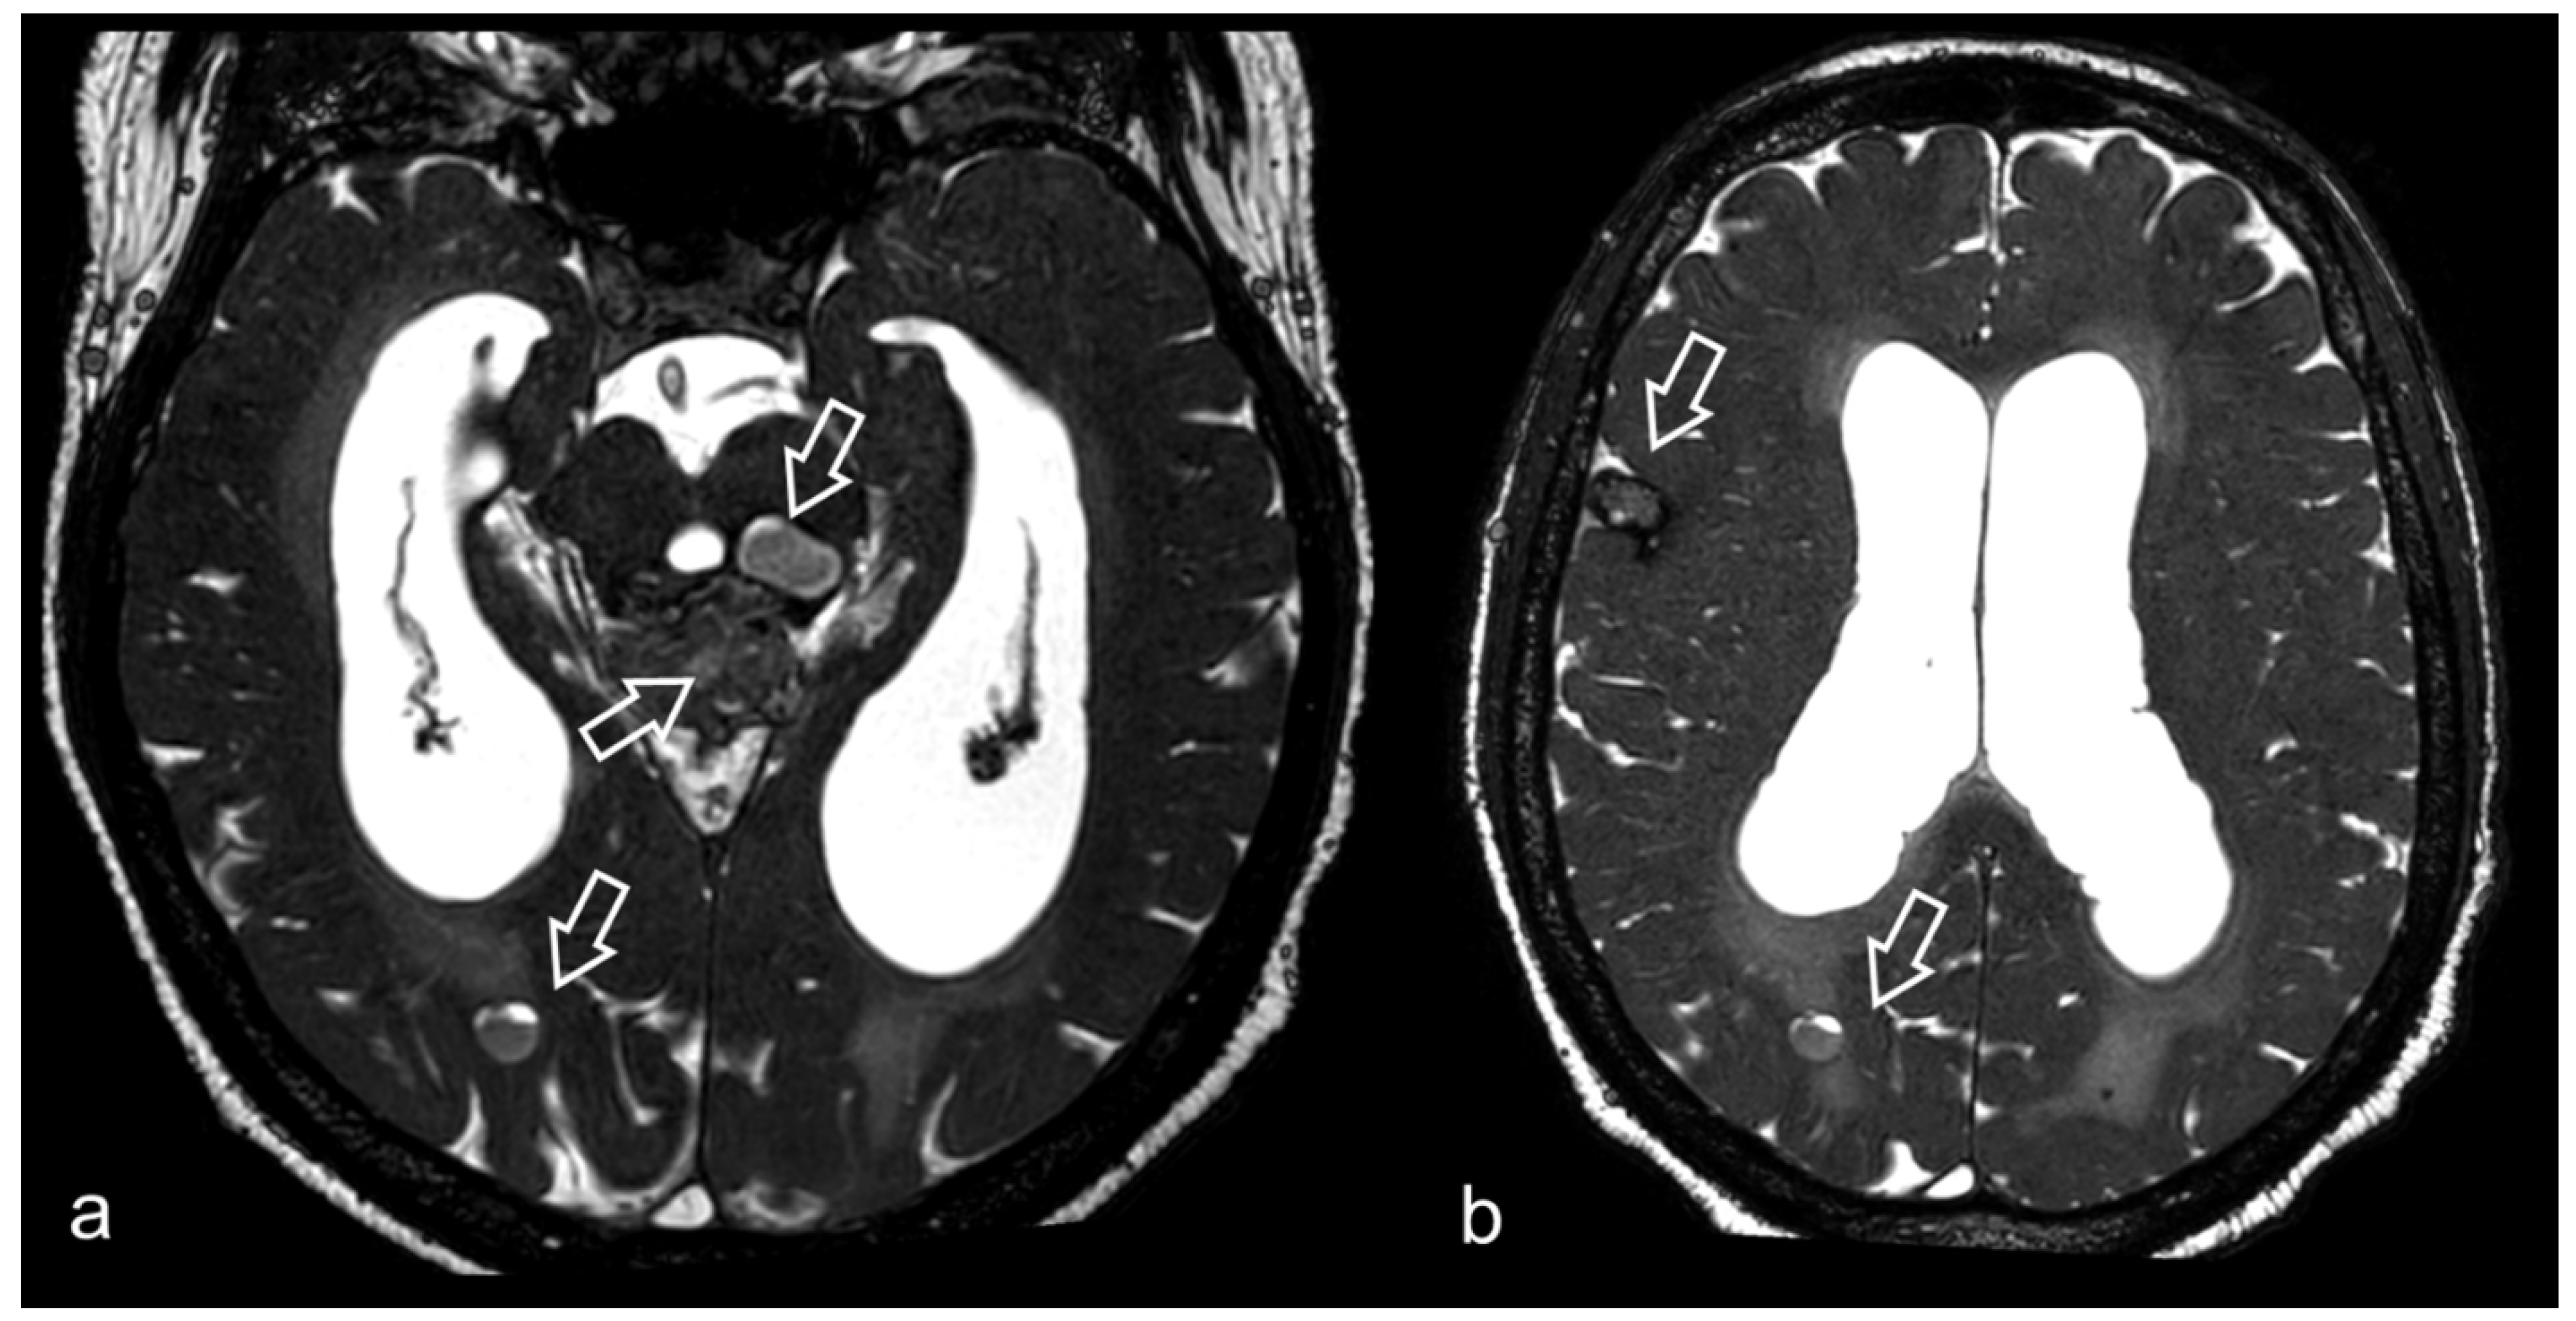

3.2. Virchow–Robin Spaces

3.5. Hydrocephalus, Ventricular System and Subarachnoid Cisterns

3.6. Neurocysticercosis